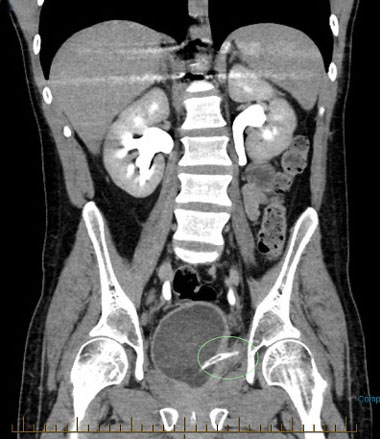

His second presentation to the same regional hospital occurred approximately 1 year later, when he presented with a 1 day history of abdominal pain, having been using long-term urethral catheterization for bladder management, changing it himself every six weeks. Computed tomography abdomen pelvis at the time of initial presentation suggested a potential perforation of bladder, and this was subsequently confirmed on a CT cystogram. Computed tomography cystogram suggested the presence of a surgical clip at the point of contrast leak from the bladder, and proposed the perforation may be at the site of the previous perforation. The proximal end of the indwelling catheter was noted to be approximately 1.5 cm outside the superior bladder wall (Figure 4). He proceeded to laparoscopic repair of bladder, found intraoperatively to have a 1 cm posterolateral injury with adherent omentum. There was purulent fluid in the pelvis which was sent for culture, and he was managed with antibiotics. An SPC was placed at this time. He recovered well post-operatively and was discharged four days post-operatively. An outpatient CT cystogram was arranged, which showed no contrast leak, and the SPC was removed 15 weeks later at patient request. A coude-tip urethral catheter was placed, with a plan to change in six weeks, or for ongoing self-catheterization.

Figure 4: Image from CT cystogram 15th April 2024 demonstrating the proximal end of the IDC located approximately 1.5 cm outside the superior bladder wall, with associated intraperitoneal contrast leak from bladder. Surgical clip noted at the site.